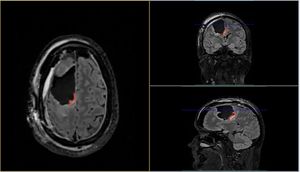

I believe there are around 4,000-5,000 images in total from 1 CT and 1 MRI scan! Thankfully there are tools that you can use to view these images. And not just view them, they allow you to navigate through all the scans. Each image is essentially a "slice" of the brain. The tools allow you to move through all 3 axis in near real time, with each of the corresponding panels changing depending on the input from the others.

In the above image you can see my MRI scan. It's essentially an orthogonal view of my head, with each of the panels represents a different axis:

- Left panel: Top of my head (Axial view)

- Top right: Front to back of my head (Coronal view)

- Bottom left: Side of my head (Sagittal view)

The solid blue line you see in the views is the current plane I have selected to see. As you move this plane, all three images change accordingly. Notice how the blue line on the axial view (left panel) matches that of the coronal view (top right) in terms of position. The resulting image in the sagittal view (bottom left) is the image that corresponds with this selection I have made.

It's so incredibly clever and absolutely fascinating (to me at least)! I spent the best part of 2-3 hours looking at my own brain scans. I wish I knew what it all meant, but I plan on quizzing the experts when I get the chance. I'd like to write a blog post all about it in the future. So, watch this space!